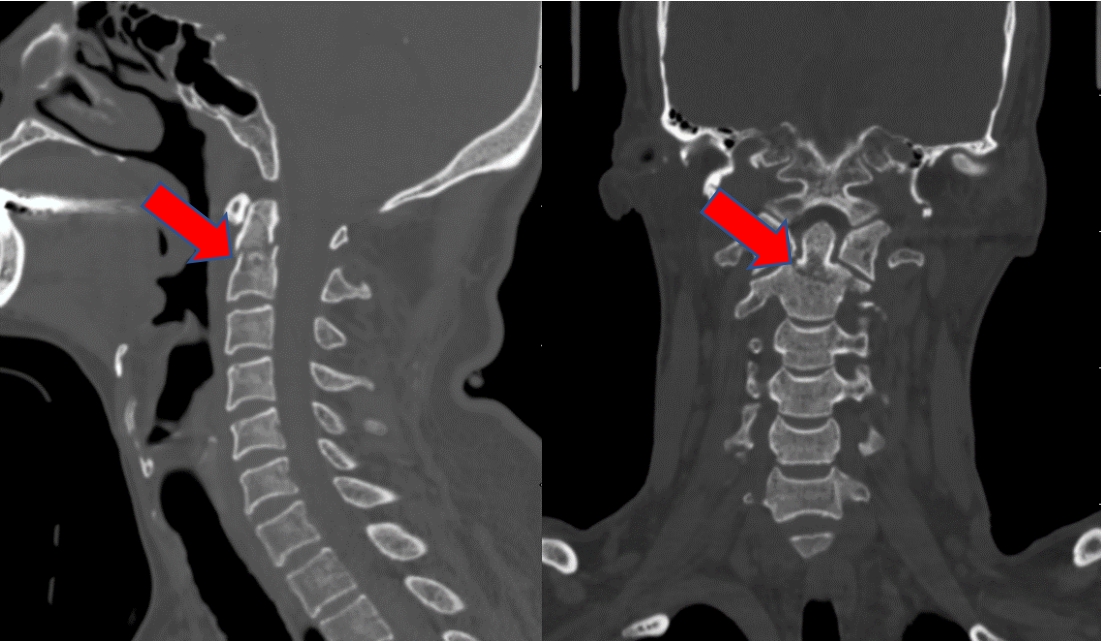

CT图像清晰显示患者C2齿状突骨折,并有移位